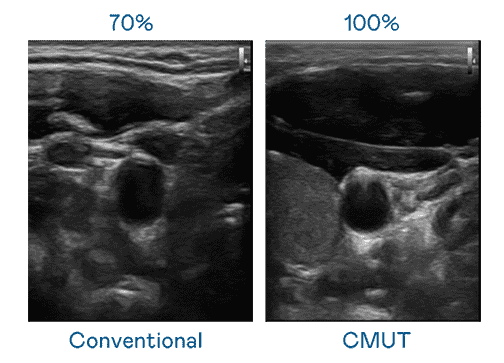

CMUT 技术是一种用电容式微机电元件来产生超音波讯号的技术。。。与传统 PZT 压电式技术相比,,CMUT 频宽增加 30%,,,更宽频的超音波讯号让影像解析度大幅提升,,是实现高影像品质医疗超音波扫描、、、、促进精准医疗发展的关键技术。。。。

大频宽带来超清晰影像

超音波影像的解析度高低,,,,首先取决于探头能发出的讯号频宽。。。巨星国际 CMUT 可提供高清晰的超音波讯号,,,提供高频宽、、高灵敏度、、影像纹理细节更高的超音波影像,,,,协助医护人员缩短影像判读时间及利用精准的医疗影像进行诊断。。